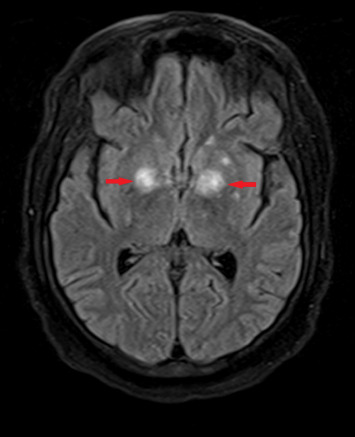

Background: Co-infection with disseminated cryptococcosis and toxoplasma encephalitis is rare but presents significant diagnostic and therapeutic challenges, particularly in severely immunocompromised patients. This case study highlights the complexities involved in managing such dual infections. Case Presentation: We describe a 43-year-old Hispanic male with Stage IV EBV-positive diffuse large B-cell lymphoma and hemophagocytic lymphohistiocytosis who presented with progressive weakness and altered mental status. Initial brain MRI revealed multiple enhancing lesions. Diagnostic tests for cryptococcosis and toxoplasma were inconclusive; however, a positive cryptococcal antigen test, new lung nodules, and potential central nervous system involvement suggested possible disseminated cryptococcosis. Diagnosis of cryptococcal meningoencephalitis could not be confirmed due to negative CSF cultures. Management and Outcome: Despite initiating treatment with amphotericin B and flucytosine for suspected cryptococcosis, the patient's condition did not improve. Initial Karius and CSF PCR tests for Toxoplasma were negative. A subsequent brain biopsy, however, confirmed toxoplasmic encephalitis. Treatment was adjusted to intravenous Trimethoprim/Sulfamethoxazole for toxoplasmosis, with continued fluconazole for cryptococcosis. The patient exhibited significant clinical improvement with this revised therapy. Conclusion: Diagnosing concurrent cryptococcal and toxoplasma infections is challenging due to overlapping clinical symptoms and variability in test sensitivities. This case underscores the need for a comprehensive diagnostic approach and the critical role of brain biopsy when other diagnostic methods, such as Karius testing and CSF PCR, are inconclusive. Prompt empirical treatment based on clinical suspicion, with subsequent treatment adjustments guided by clinical response and follow-up assessments, is essential for effective management.

Abstract Image